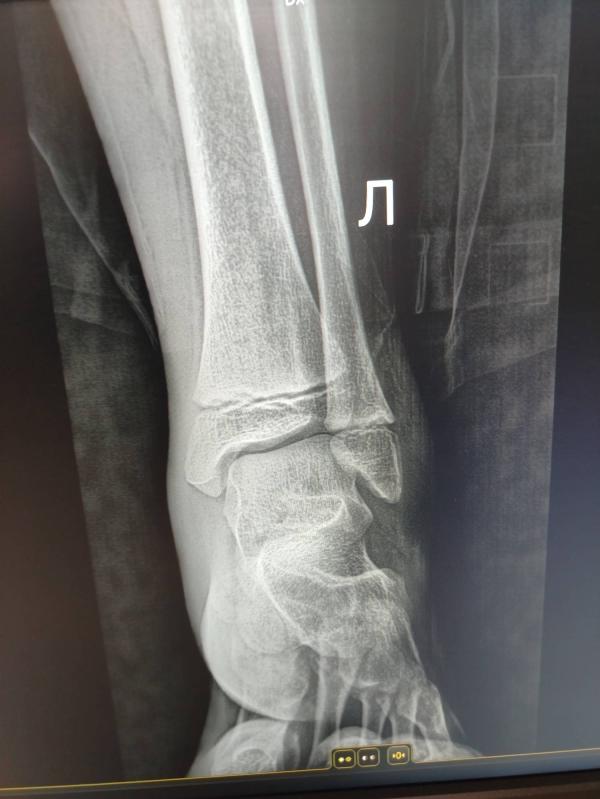

Девочки, может есть среди нас врач, который по снимку может определить повреждения ноги. Дочь ещё 13го числа на батуте сильно потянула ногу. Ездили в травму. Врач по снимку сказал растяжение сильное. Ноге, конечно, лучше, синяк меньше стал и отёк уменьшается. Но уже так долго не проходит. Думаю, надо ещё к кому-то ехать. Может он плохо посмотрел.